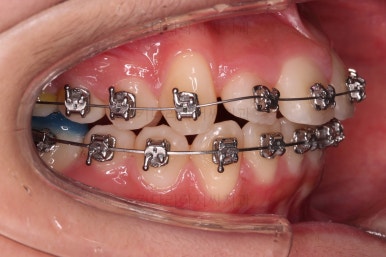

이번 환자분이 선택하신 장치는 엠파워 메탈이라고 하는 자가결찰 금속 장치에요.

메탈 장치라고 모두 구식의 옛날 안좋은 장치라고 생각하시면 안되고, 자가결찰 인지 아닌지 여부가 훨씬 중요하다고 거듭 말씀드렸지요.

자가결찰이기만 하면 치료 효과 동일하며, 단지 성분이 메탈이냐 세라믹이냐에 따라 보이는 정도, 부피, 모양 등이 약간 차이가 있을 뿐이에요.

가지런하게 하면서 안으로 쏙 들어가있는 앞니를 가지런하게 할 자리 확보부터 해줍니다.

자리 확보 이 후에 가지런하게 해주는데요.